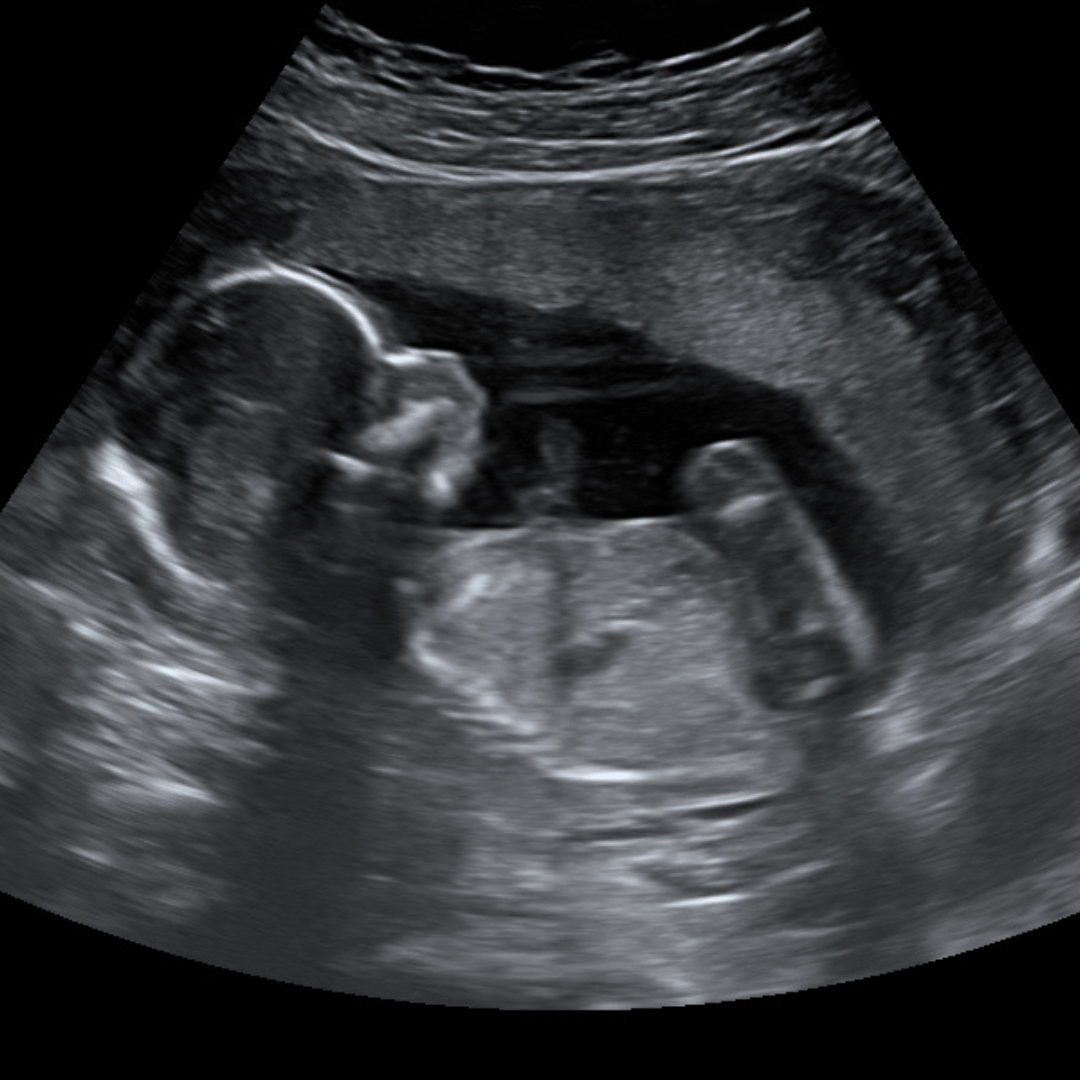

Peace of Mind

6-13 weeks – $50 (recommended 6-13 wks)

Congratulations on your new bundle of joy! See a glimpse of your baby growing starting at 6 weeks!

*Please come in with a full bladder (before 10 weeks) for the best view of your baby*

- 5-10 minute session

- THIS IS A 2D ULTRASOUND

- Printed black & white pictures (Strip)

- Measure baby’s heartbeat (6 weeks +)

- Listen to baby’s heartbeat (9 weeks +)